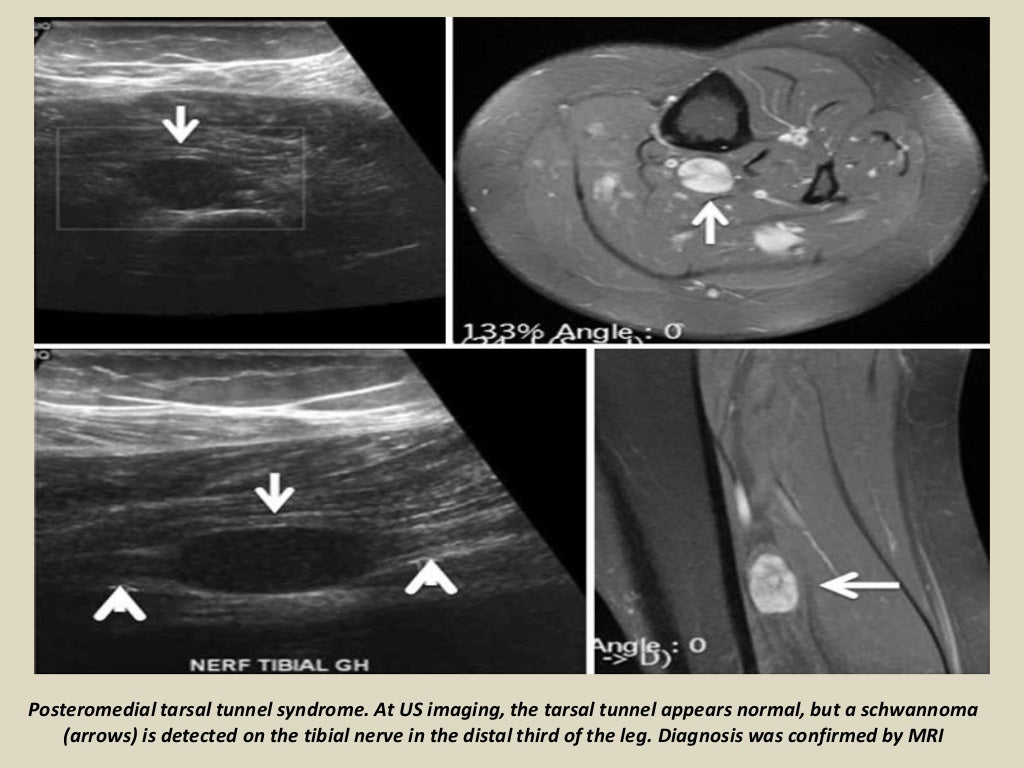

Presentation1 radiological imaging of tarsal tunnel syndrome.

Presentation1 radiological imaging of tarsal tunnel syndrome. Tarsal Tunnel Syndrome X Ray Tarsal tunnel syndrome refers to an entrapment neuropathy (tunnel syndrome) of the (posterior) tibial nerve or of its branches within the tarsal tunnel. Tarsal tunnel syndrome refers to an entrapment neuropathy (tunnel syndrome) of the (posterior) tibial nerve or of its branches within. Mr imaging can accurately depict the contents of the tarsal tunnel and the courses of the terminal. Tarsal Tunnel Syndrome X Ray.

Presentation1 radiological imaging of tarsal tunnel syndrome. Tarsal Tunnel Syndrome X Ray This condition is analogous to carpal tunnel. Tarsal tunnel syndrome is a compressive neuropathy of the tibial nerve at the level of the tarsal tunnel which can lead to pain. Tarsal tunnel syndrome (tts) is a common entrapment syndrome whose diagnosis can be difficult. Tarsal tunnel syndrome refers to an entrapment neuropathy (tunnel syndrome) of the (posterior) tibial nerve or. Tarsal Tunnel Syndrome X Ray.

Presentation1 radiological imaging of tarsal tunnel syndrome. Tarsal Tunnel Syndrome X Ray This condition is analogous to carpal tunnel. Tarsal tunnel syndrome is a compressive neuropathy of the tibial nerve at the level of the tarsal tunnel which can lead to pain. Tarsal tunnel syndrome refers to an entrapment neuropathy (tunnel syndrome) of the (posterior) tibial nerve or of its branches within the tarsal tunnel. Tarsal tunnel syndrome refers to an entrapment. Tarsal Tunnel Syndrome X Ray.